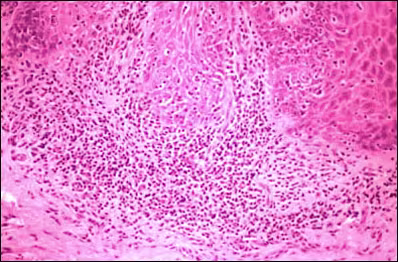

Subjacent to the epithelium was a band of chronic inflammatory cells, which in some areas effaced the rete ridge architecture. (Figure 3) A perivascular infiltrate comprised mostly of lymphocytes, with occasional plasma cells, was seen in association with the vascular channels in the connective tissue. Upon staining with the periodic acid-Schiff (PAS) method, no evidence of fungal forms was identified in the superficial epithelium.

Figure 3.